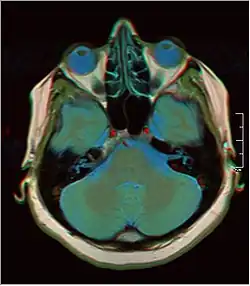

Cross-sectional T1-weighted MRI of a healthy human brain acquired with an ultra high-field MR of 7 Tesla field strength

False color MRI by applying red to T1, green to PD and blue to T2.